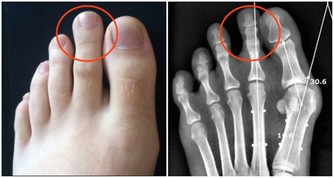

大量的生長激素會刺激骨關節異常增生,侵犯膝、踝、腕等大關節,出現腫脹、疼痛等症狀。